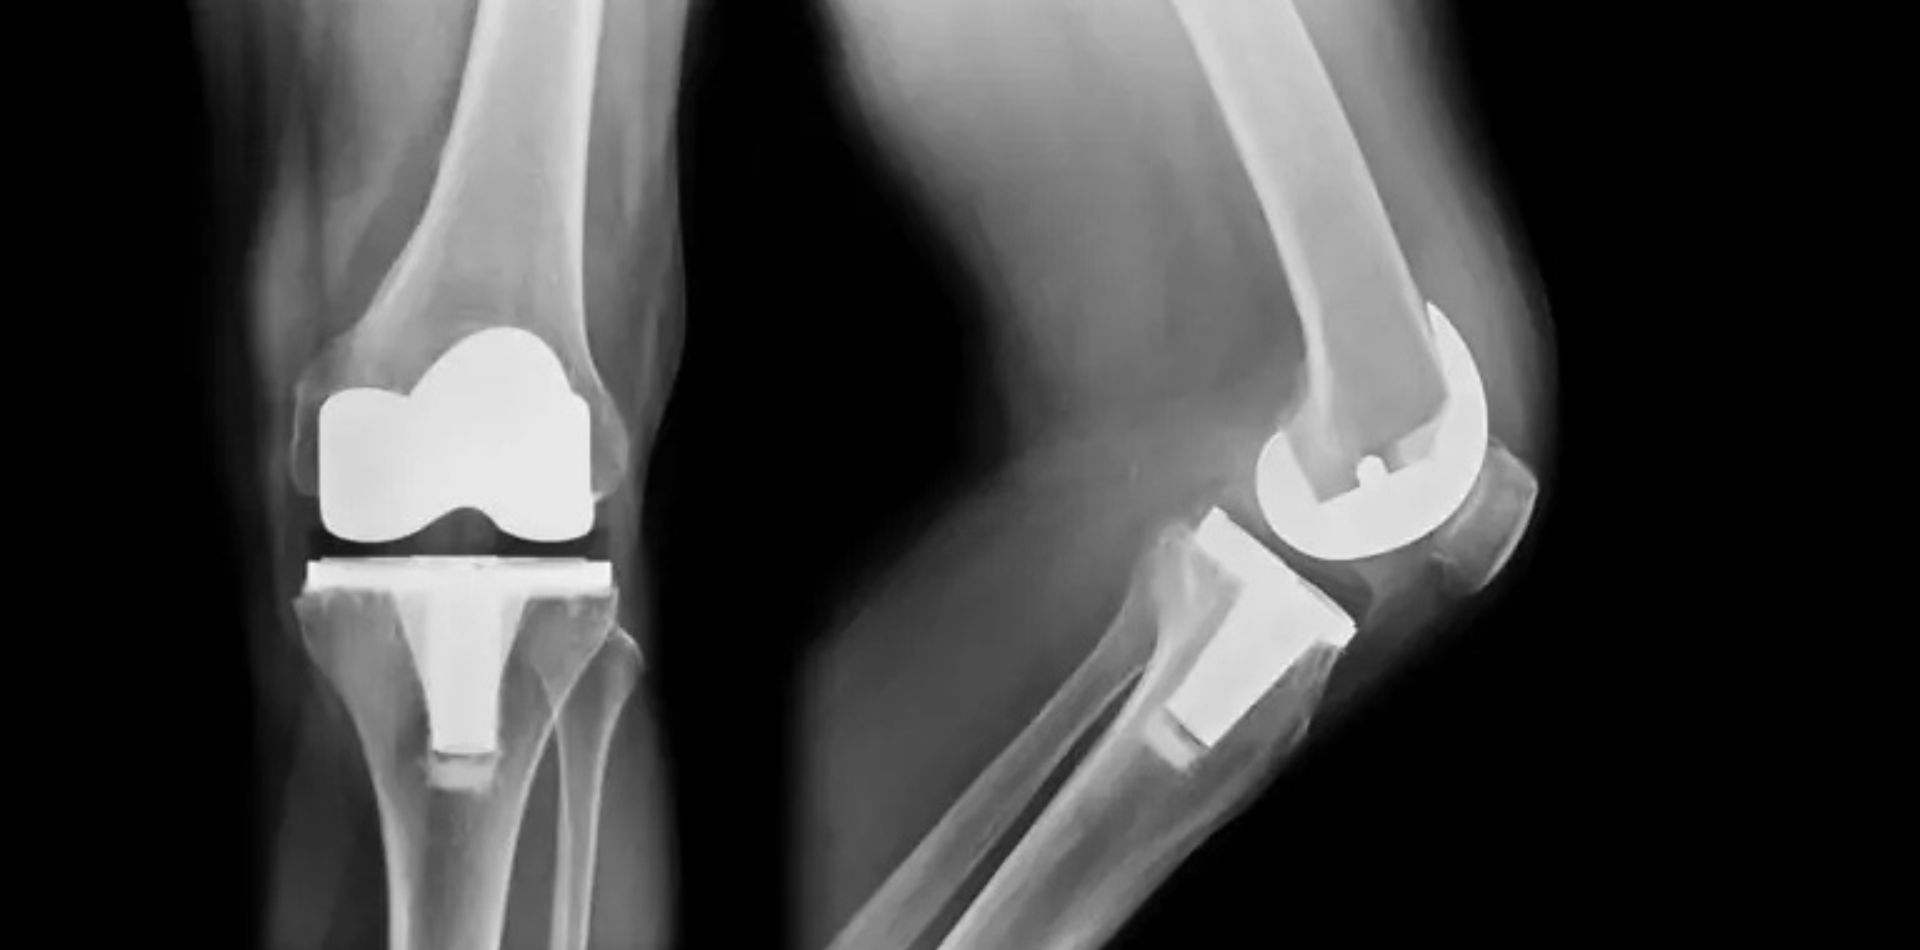

NCMT supports medical manufacturers across the UK and Ireland with high-technology CNC machine tools, automation systems and engineering expertise designed for precision-driven production environments. From orthopaedic implants to surgical instruments and medical housings, we help you achieve consistent quality and controlled manufacturing performance.

Medical components frequently require micron-level accuracy, fine surface finishes and reliable machining of challenging materials such as stainless steels, cobalt chrome, titanium alloys and specialist polymers.

• High-accuracy 5-axis machining centres for complex implant geometries